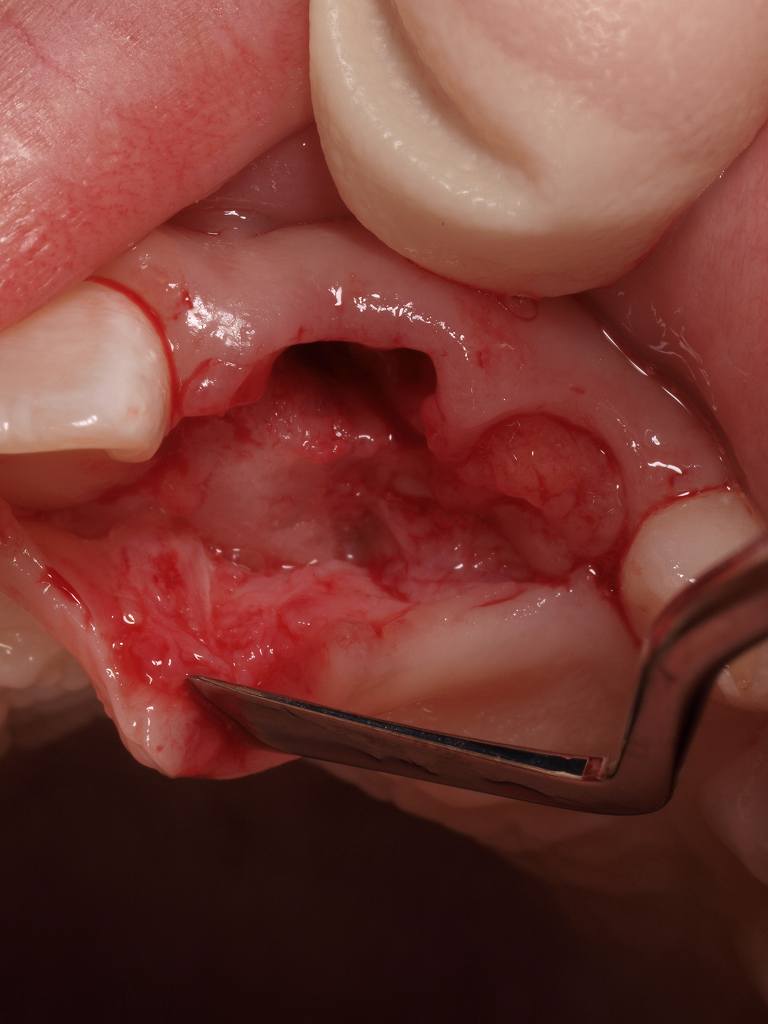

乳歯を抜歯した後、骨内にある過剰歯を抜歯していきます

縫合して終了です

まだ9歳のお子さんにする処置としては忍びないのですが、、

少しでも早い方がいいです